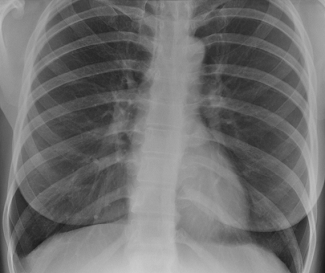

Рентгеноскопия органов грудной клетки

Рентгеноскопия органов грудной клетки в

онкологической практике применяется как дополнительный метод исследования в

дифференциальной диагностике центрального рака легкого: чем хуже пульсация

пораженного корня легкого, тем менее вероятна его сосудистая патология и более

вероятна опухолевая природа изменений.

Врачи-рентгенологи могут применять

рентгеноскопию грудной клетки при периферических образованиях в легких, если

таковые видны только на прямой рентгенограмме, но не определяются в других

проекциях - для выбора оптимального среза линейной томографии.

Рентгенография легких, норма

Рак легких